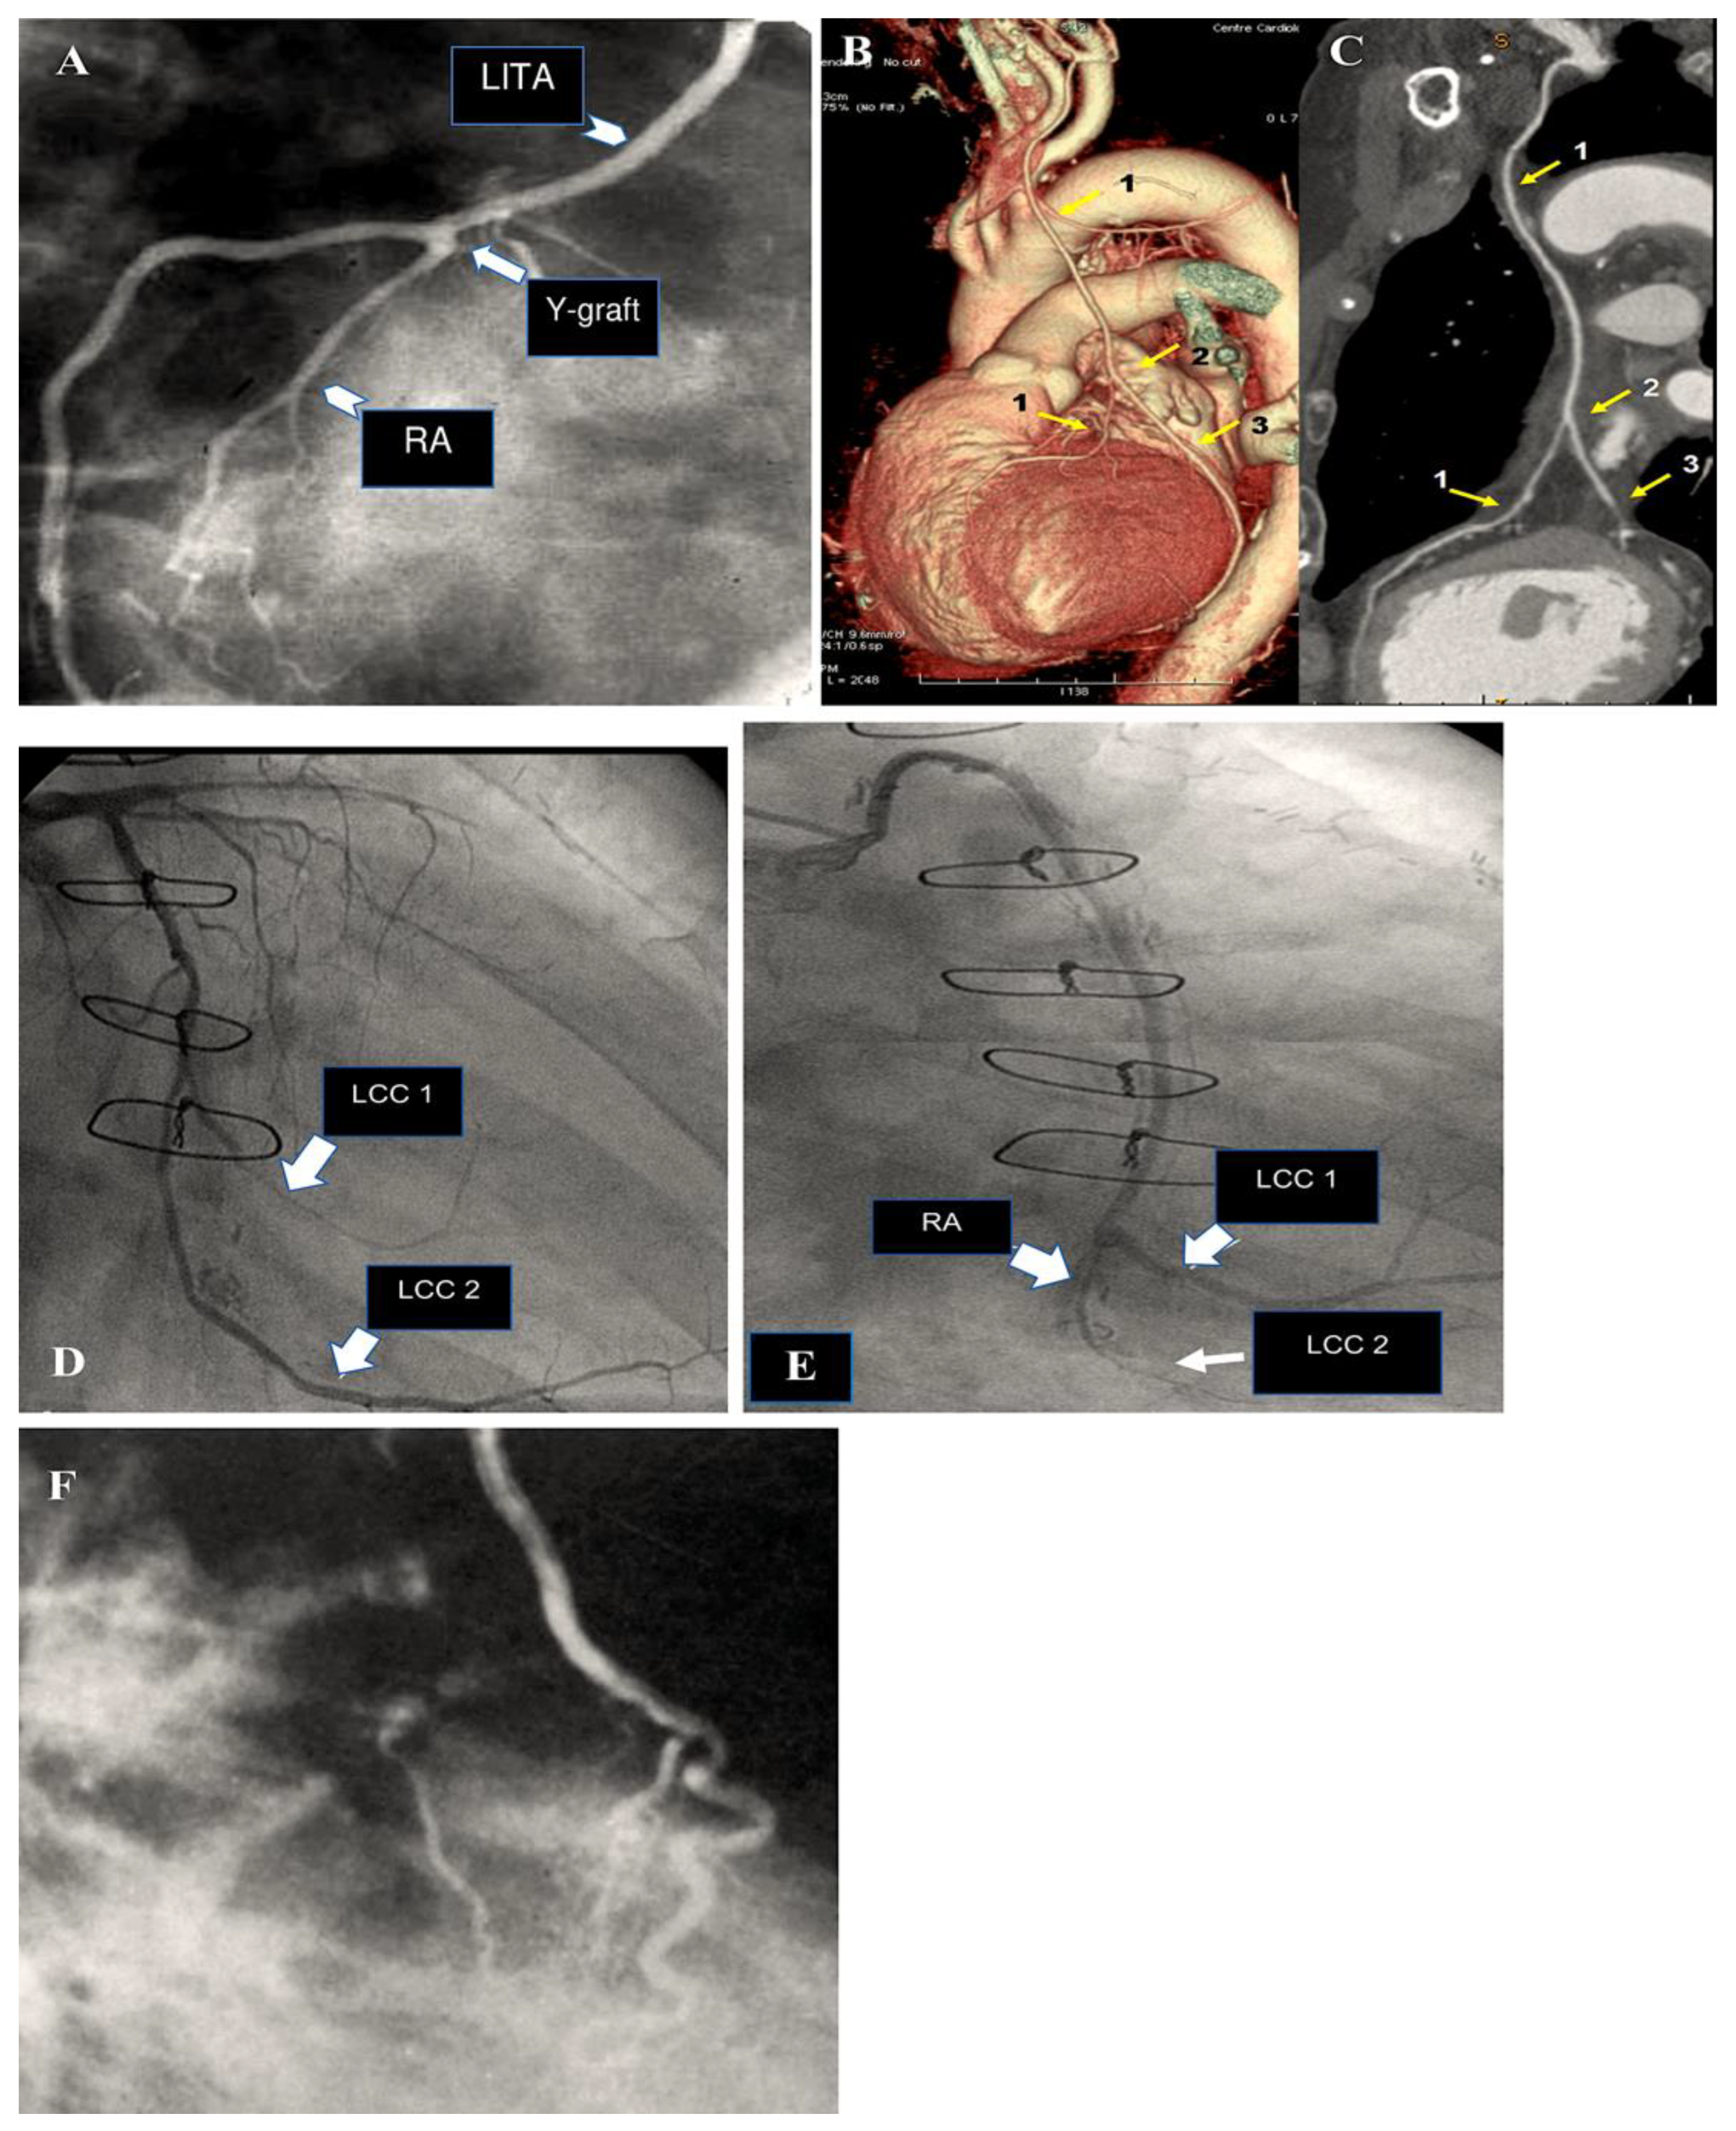

- Goube P, Hammoudi N, Pagny JY, Boutekadjirt R, Toledano D, Achouh P, Acar C. Radial artery graft stenosis treated by percutaneous intervention. Eur J Cardiothorac Surg 2010. 37:697-703. [CrossRef]